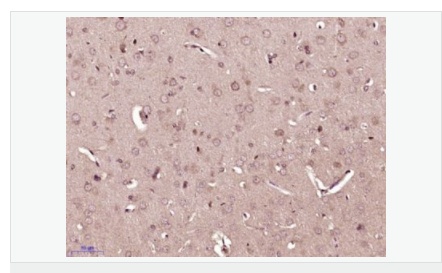

| 產品應用 | WB=1:500-2000 ELISA=1:5000-10000 IHC-P=1:100-500 IHC-F=1:100-500 IF=1:100-500 (石蠟切片需做抗原修復) not yet tested in other applications. optimal dilutions/concentrations should be determined by the end user. |

| 產品介紹 | BM88 is a 149 amino acid protein that belongs to the CEND1 familly. Involved in neuroblastoma cell differentiation, BM88 is a single-pass type IV membrane protein that is neuron specific. It is suggested that BM88 forms a dimer of two identical polypeptides linked by disulfide bridges. BM88 has a central proline-rich region containing four PxxP motifs, which typically bind SRC homology-3 (SH3) domains, as well as a putative C-terminal transmembrane region, and several potential sites for N-glycosylation, myristoylation and phosphorylation. It is also suggested that a novel signaling mechanism exists by which BM88 interferes with calcium release from inositol 1,4,5-trisphosphate-sensitive stores and exerts anti-proliferative and anti-apoptotic functions. BM88 is an important molecular target for HDAC inhibition, and transcription of BM88 is induced by trichostatin-A. Function: CEND1 is a neuron-specific protein. The similar protein in pig enhances neuroblastoma cell differentiation in vitro and may be involved in neuronal differentiation in vivo. Multiple pseudogenes have been reported for this gene. Subunit: Homodimer Subcellular Location: Membrane; Single-pass type IV membrane protein. Tissue Specificity: Neuron specific. Similarity: Belongs to the CEND1 family. SWISS: Q8N111 Gene ID: 51286 Database links: Entrez Gene: 51286 Human Entrez Gene: 57754 Mouse Omim: 608213 Human SwissProt: Q8N111 Human SwissProt: Q9JKC6 Mouse Unigene: 22140 Human Unigene: 87027 Mouse Unigene: 64460 Rat Important Note: This product as supplied is intended for research use only, not for use in human, therapeutic or diagnostic applications. |